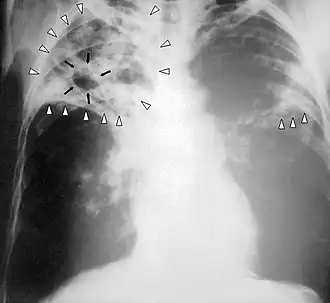

Sogosogonice (Tuberculosis) walima TB ye bana yelemata ye min be mogo faga.